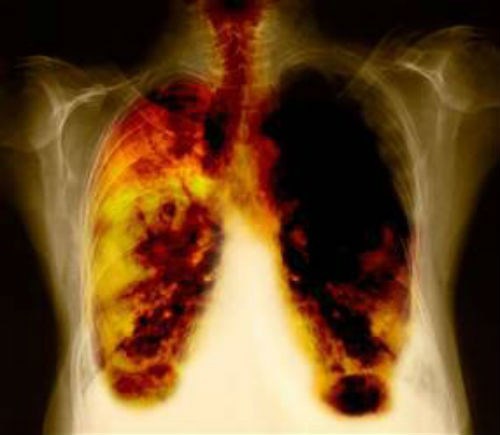

Hít khí than tổ ong, người phụ nữ có phổi đen xì

Mặc dù không hút thuốc lá nhưng phổi chị Nguyễn Thùy Dương lại bị đen xì khiến cả nhà đều rất sốc.